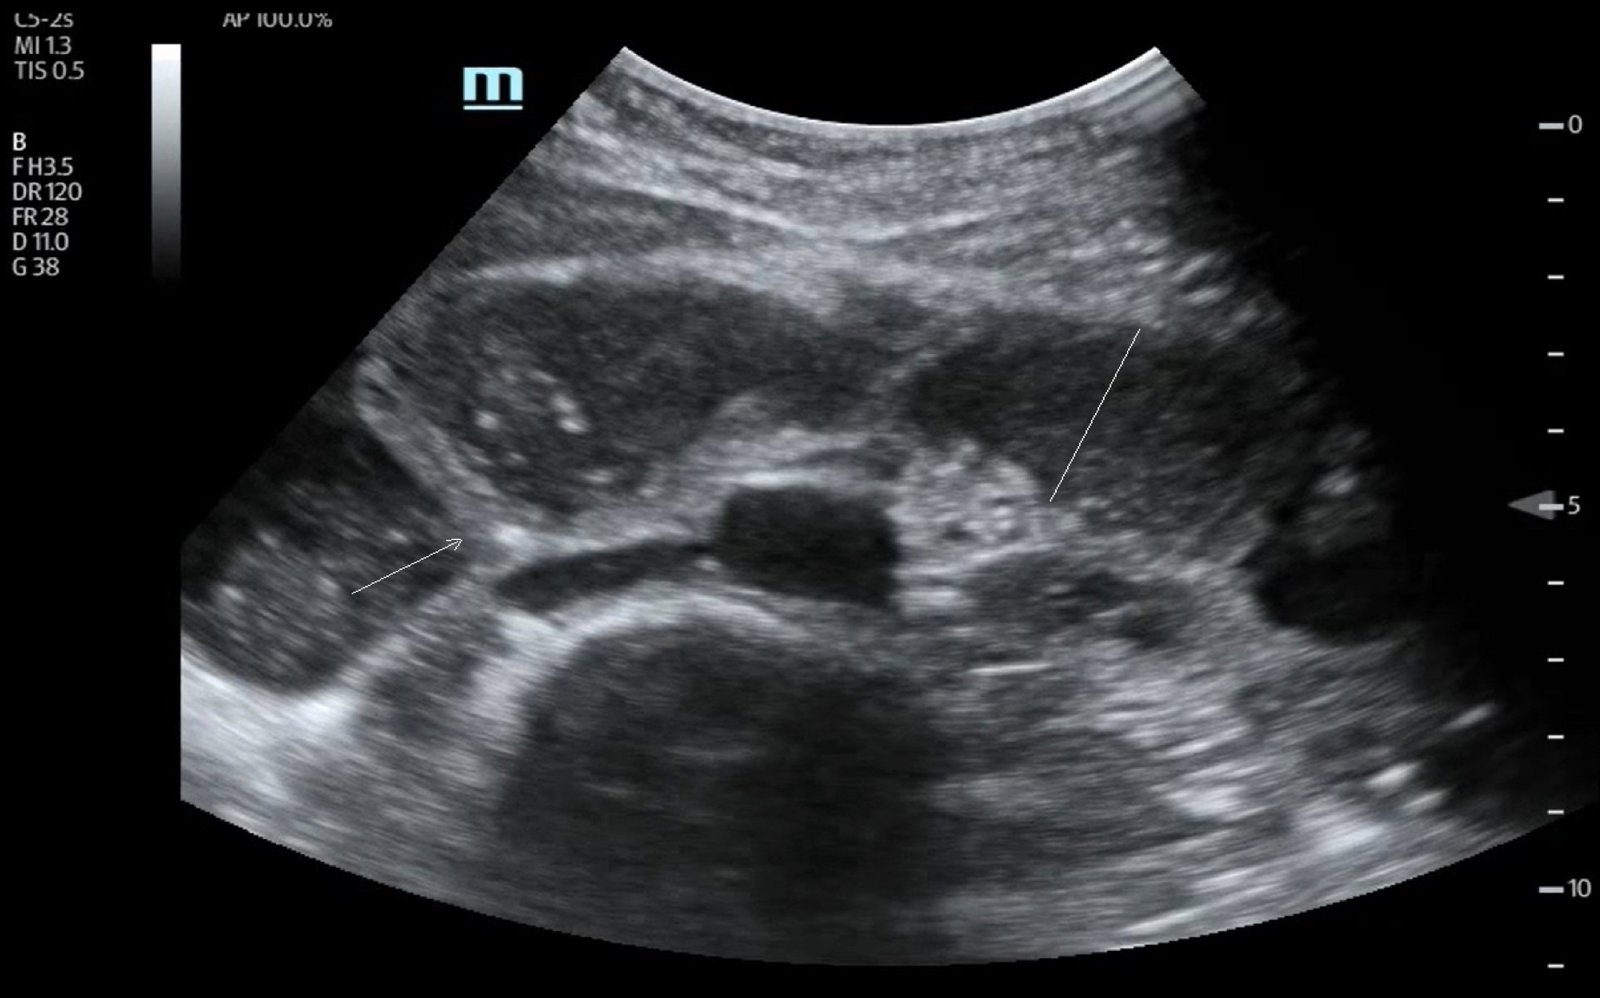

POCUS of the small bowel illustrated significantly dilated loops of bowel (white line), thickened bowel wall (white arrow) and to-and-fro peristalsis, consistent with small bowel obstruction.

Approximately two percent of patients who present to the ED with abdominal pain are diagnosed with SBO.1-2 POCUS has been shown to have a sensitivity of 92.4% and specificity of 96.6% for the diagnosis of SBO.3 The proper way to scan patients with suspected SBO is by using the curvilinear probe (3-5 MHz) across the entire abdomen. Pathologic findings include bowel dilatation (which can be measured from the inner wall to the inner wall of the small bowel) greater than 2.5cm. Other positive findings include to-and-fro peristalsis, mesenteric thickening and thickening of valvulae conniventes. Wall thickening greater than 3 mm and free fluid between bowel loops may suggest bowel ischemia.4 Despite the high diagnostic accuracy of the POCUS, it can be operator dependent and is limited by the ability to accurately identify a transition point. CT scan also has the advantage of determining the underlying cause and identifying the exact location of the obstruction.5